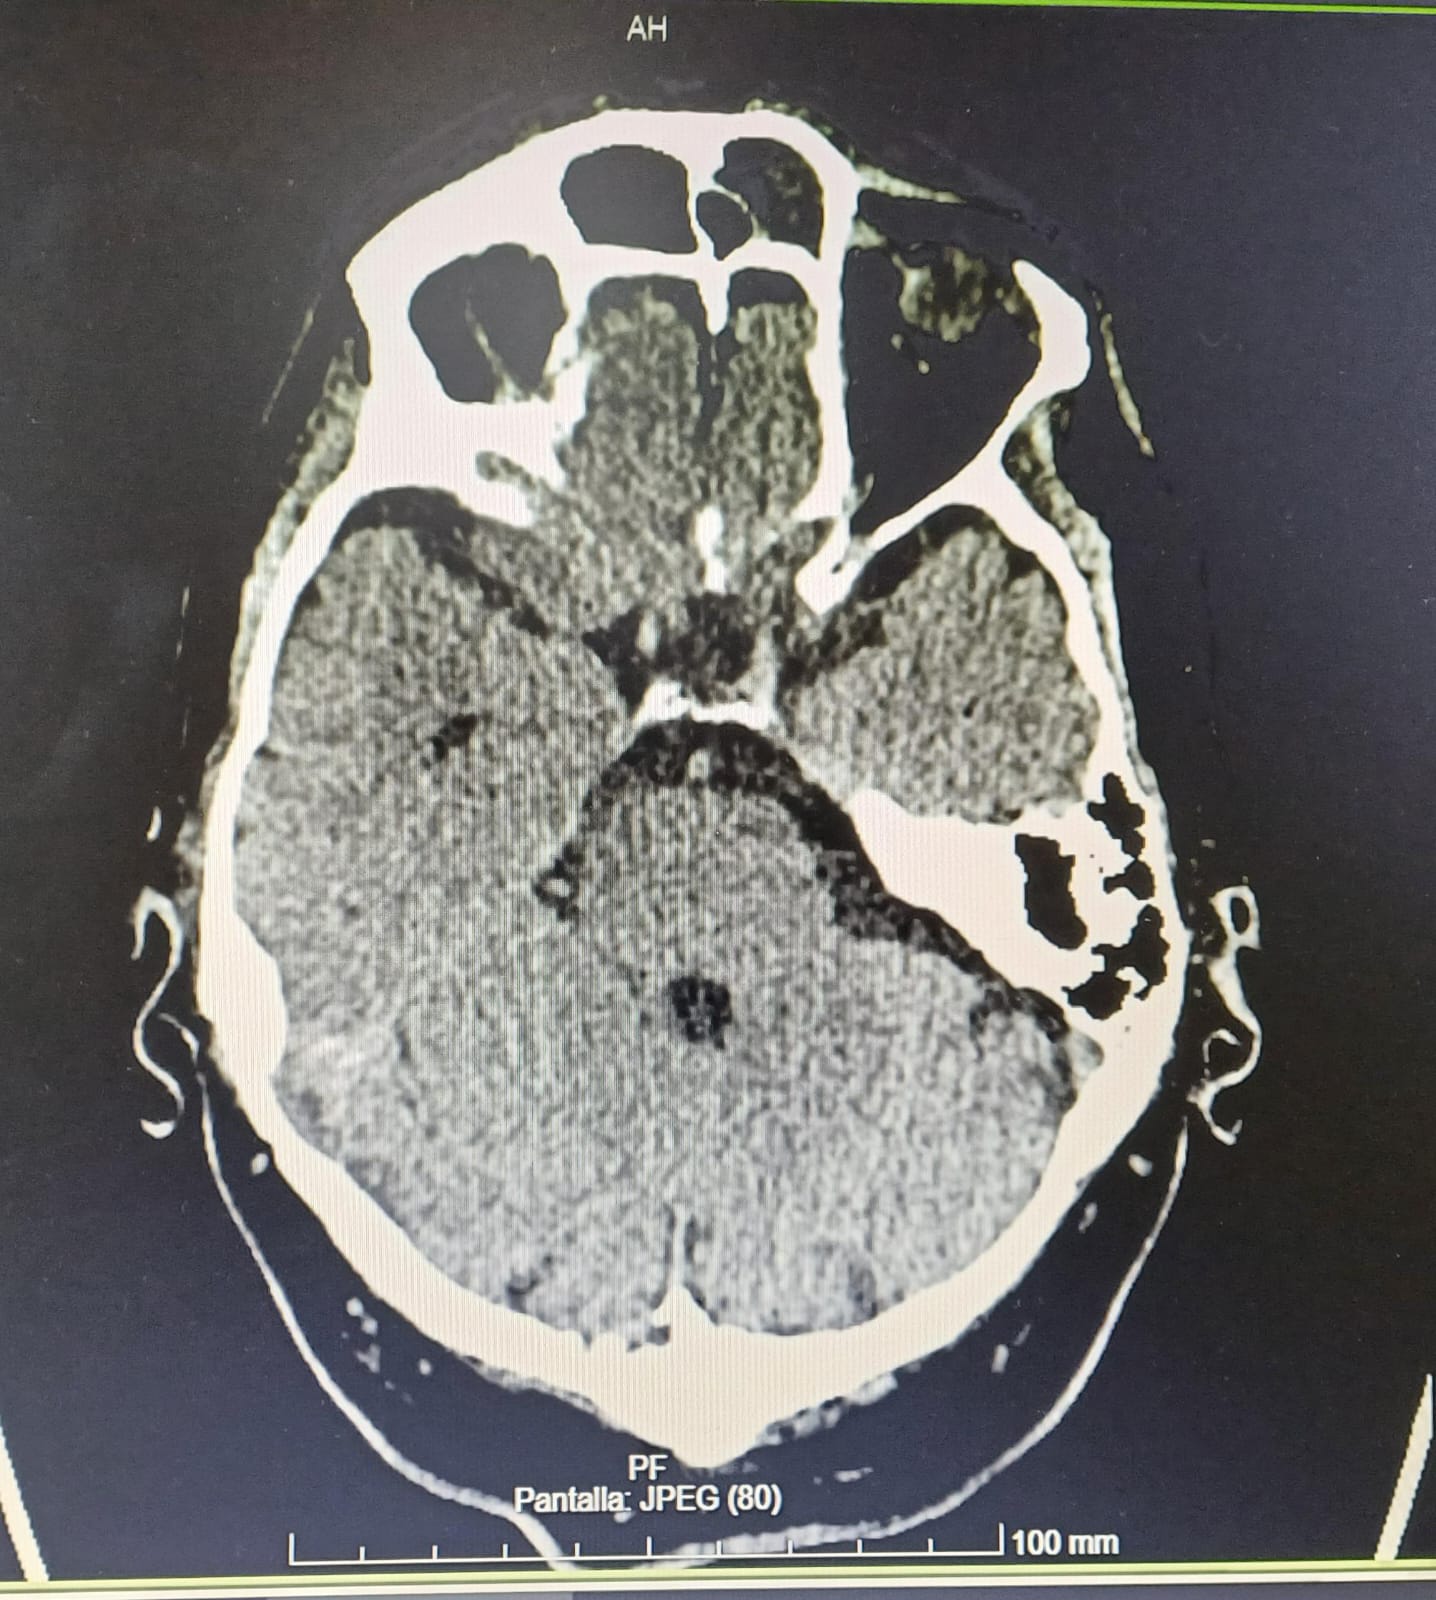

Meningoencefalitis otógena secundaria a OMA. Empiema subdural derecho. Tromboflebitis séptica en seno sigmoide y transverso distal derechos. Hemorragia subaracnoidea.

Manejo conservador conjunto Otorrinolaringología (ORL)y Neurología (NRL). Ante situación clínica se traslada a Unidad de Críticos y posteriormente ingreso en UMI para neurovigilancia con buena evolución. Seguimiento con TC y RNM cráneo y oído presentando ocupación de oído medio y celdillas mastoideas derechas, solución de continuidad en techo de mastoides con gas intracraneal. Empiema subdural en convexidad derecha 6 mm (previo 3 mm). Ante febrícula y leucocitosis mantenida se realiza nueva PL, con incremento de glucorraquia y sin gérmenes, se amplía antibioterapia a meropenem con buena evolución clínica posterior. Alta a planta de NRL con seguimiento por Unidad de Enfermedades Infecciosas.